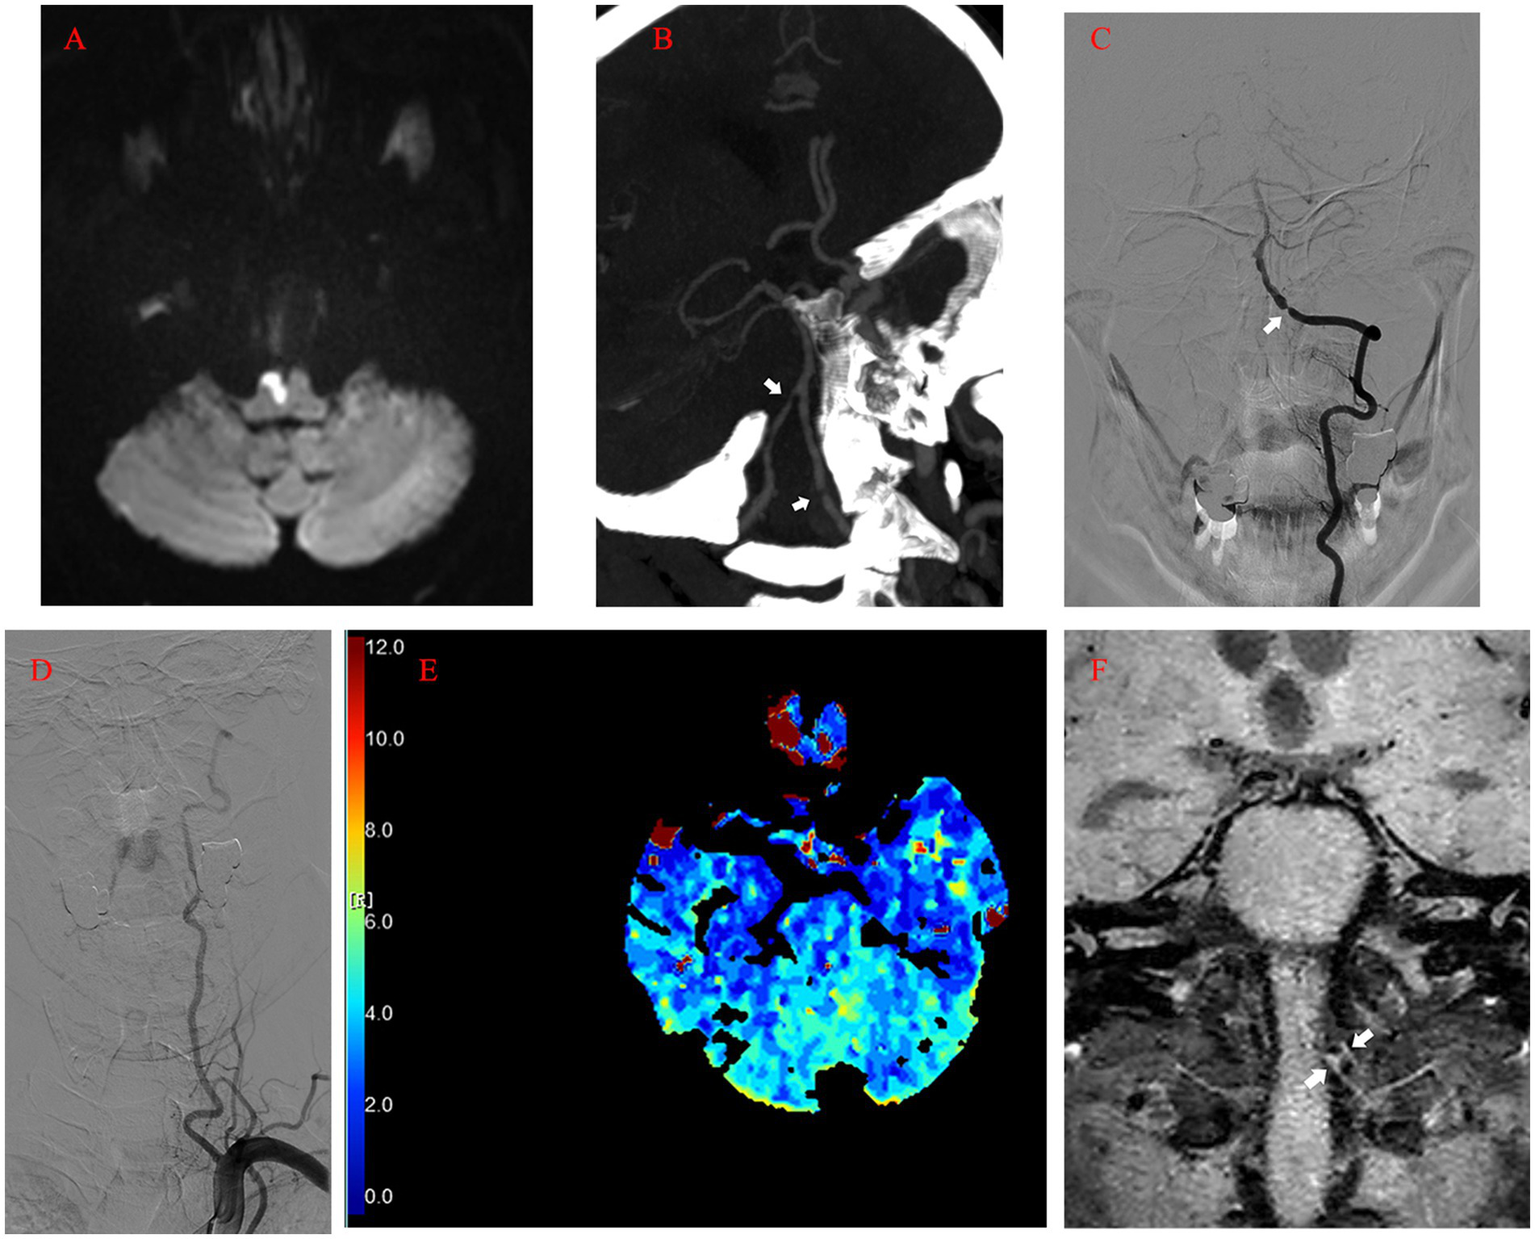

A 56-year-old male presented with worsening dizziness and left-sided hemiplegia overnight. The patient’s medical history included 10-year-long hypertension and type 2 diabetes. The physical examination on admission revealed grade 0 muscle strength in the upper left extremity, grade 3 muscle strength in the lower left extremity, and left-sided hypoesthesia (Table 1). MRI demonstrated a new-onset ischemic stroke in the right anteromedial medulla oblongata (Figure 1A) and an old hemorrhage in the right medial pons. Computed tomography angiography (CTA) revealed bilateral VA stenosis in the intracranial segment (Figure 1B). Later digital subtraction angiography (DSA) confirmed this result, demonstrating a preocclusive (> 90%) narrowing of the left intracranial VA and tortuosity of the left VA (Figures 1C,D). We also found marked hypoperfusion in the brain stem and cerebella by computed tomography perfusion (Figure 1E). High-resolution MRI revealed atheromatous plaques in the stenotic segment of the left VA (Figure 1F). The patient’s state had remarkably improved at discharge after treatment and rehabilitation.

Figure 1

(A) Acute infarction of the right anteromedial medulla oblongata visualized by MRI (diffusion-weighted imaging). (B) Computed tomography angiography image showing the bilateral VA stenosis in the intracranial segment (arrow). (C) Left vertebral angiogram (anterior–posterior view) showing preocclusive stenosis of the left intracranial VA (arrow). (D) Tortuosity of the left VA revealed by angiogram. (E) Computed tomography perfusion showing the marked hypoperfusion in the brain stem and cerebella (Tmax). (F) High-resolution MRI showing atheromatous plaques (arrow) in the stenotic segment of the left VA (coronal view). MRI, magnetic resonance imaging; VA, vertebral artery; Tmax, Time to Max.